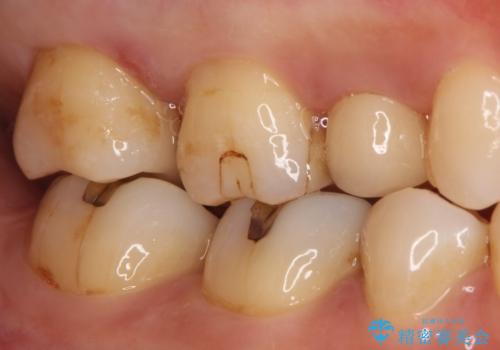

【セラミックインレー】虫歯の治療

- 虫歯を認めたため、セラミックインレーにて治療を行いました。

見た目も綺麗に修復することができ患者様には満足していただきました。

- 7万円費用は治療当時の料金となります

セラミックインレーの接着には必ずラバーダム防湿を行なっています。